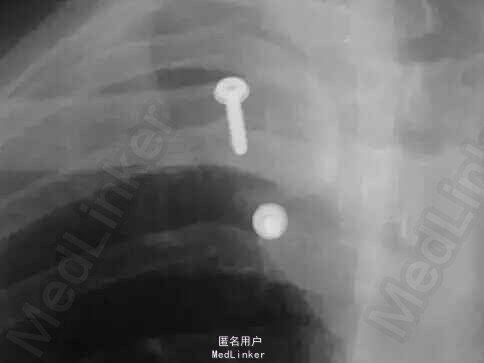

查体:胸前部略肿胀,左侧胸锁关节处隆起,触痛,可触及浮动感,左肩活动时疼痛加重,余未见异常。 辅检:门诊X线片:左侧胸锁关节脱位

诊断:左侧胸锁关节脱位 治疗:行切开复位内固定术,应用两枚螺钉及不可吸收线八字固定

随访,讨论:术后维持患肩制动,预防感染,功能锻炼,对症治疗。手术过程简便,恢复良好。